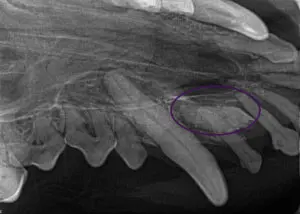

She received an annual cleaning around a year ago at her family veterinarian’s hospital. Today, there is Stage 4 periodontal disease (>50% bone loss) on the maxillary and mandibular incisors. In addition, there is an embedded right maxillary 3rd incisor (circled purple in 2nd image). The visible right 3rd incisor is a primary tooth (puppy). The sneezing was due to the fact the embedded incisor was in the nasal canal, causing chronic pathology.